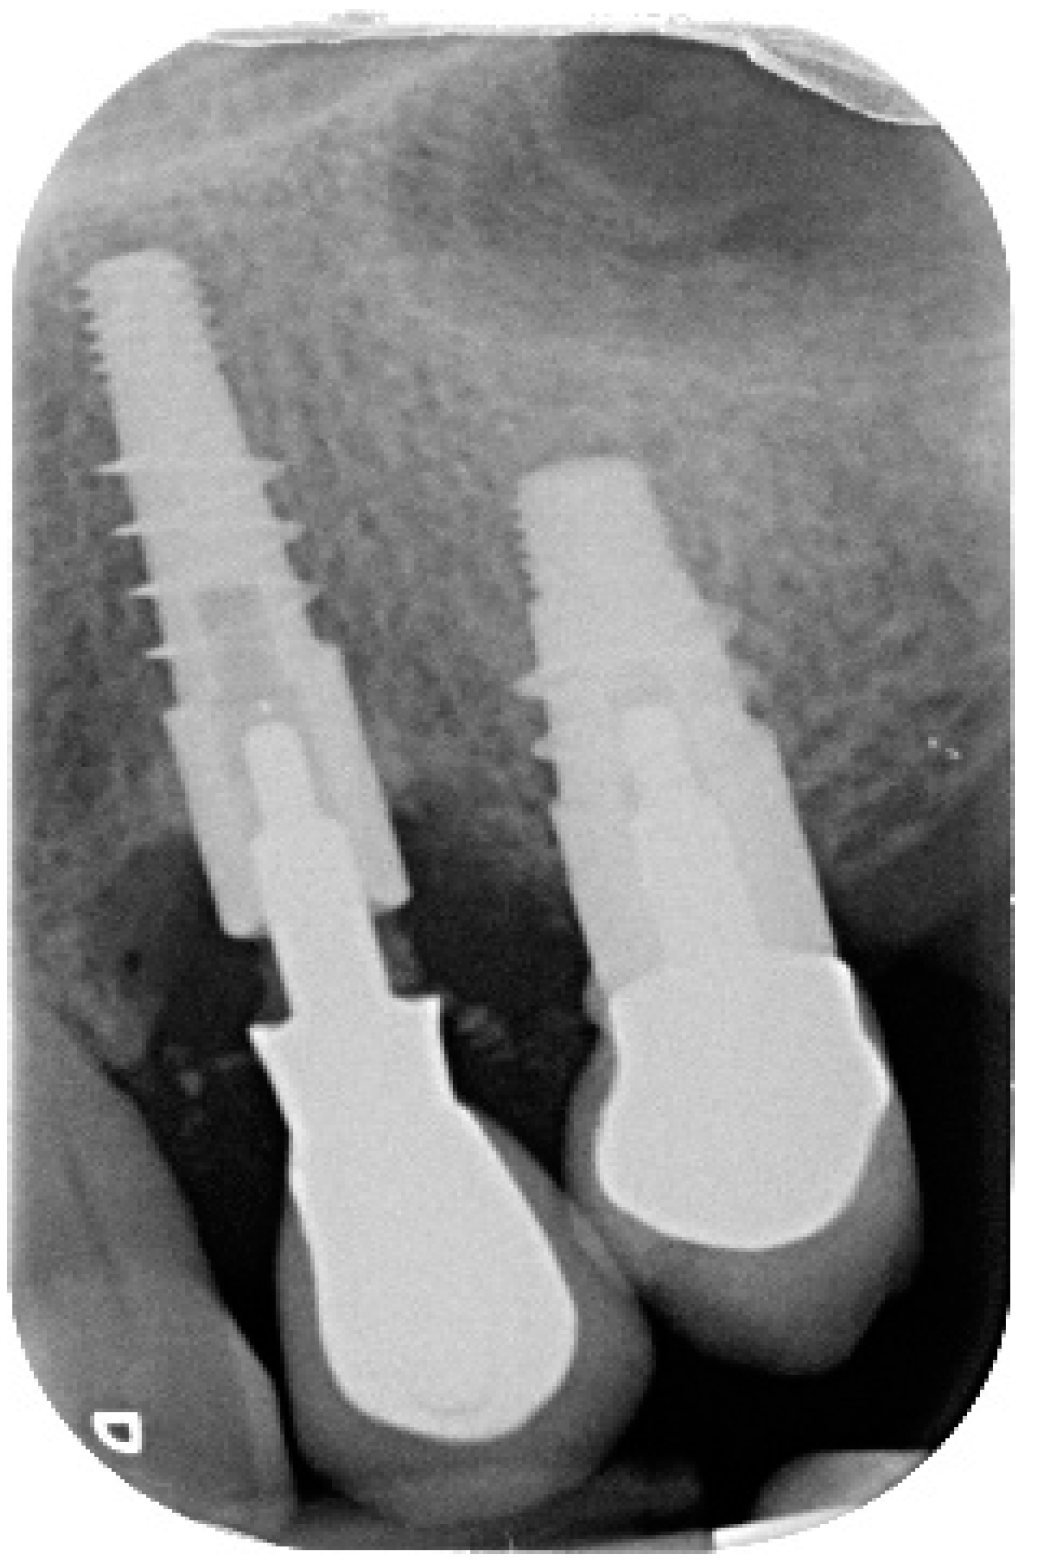

3. Discussion

4.1. Surgical Procedure for Open Flap Debridement

4.2. Clinical Case